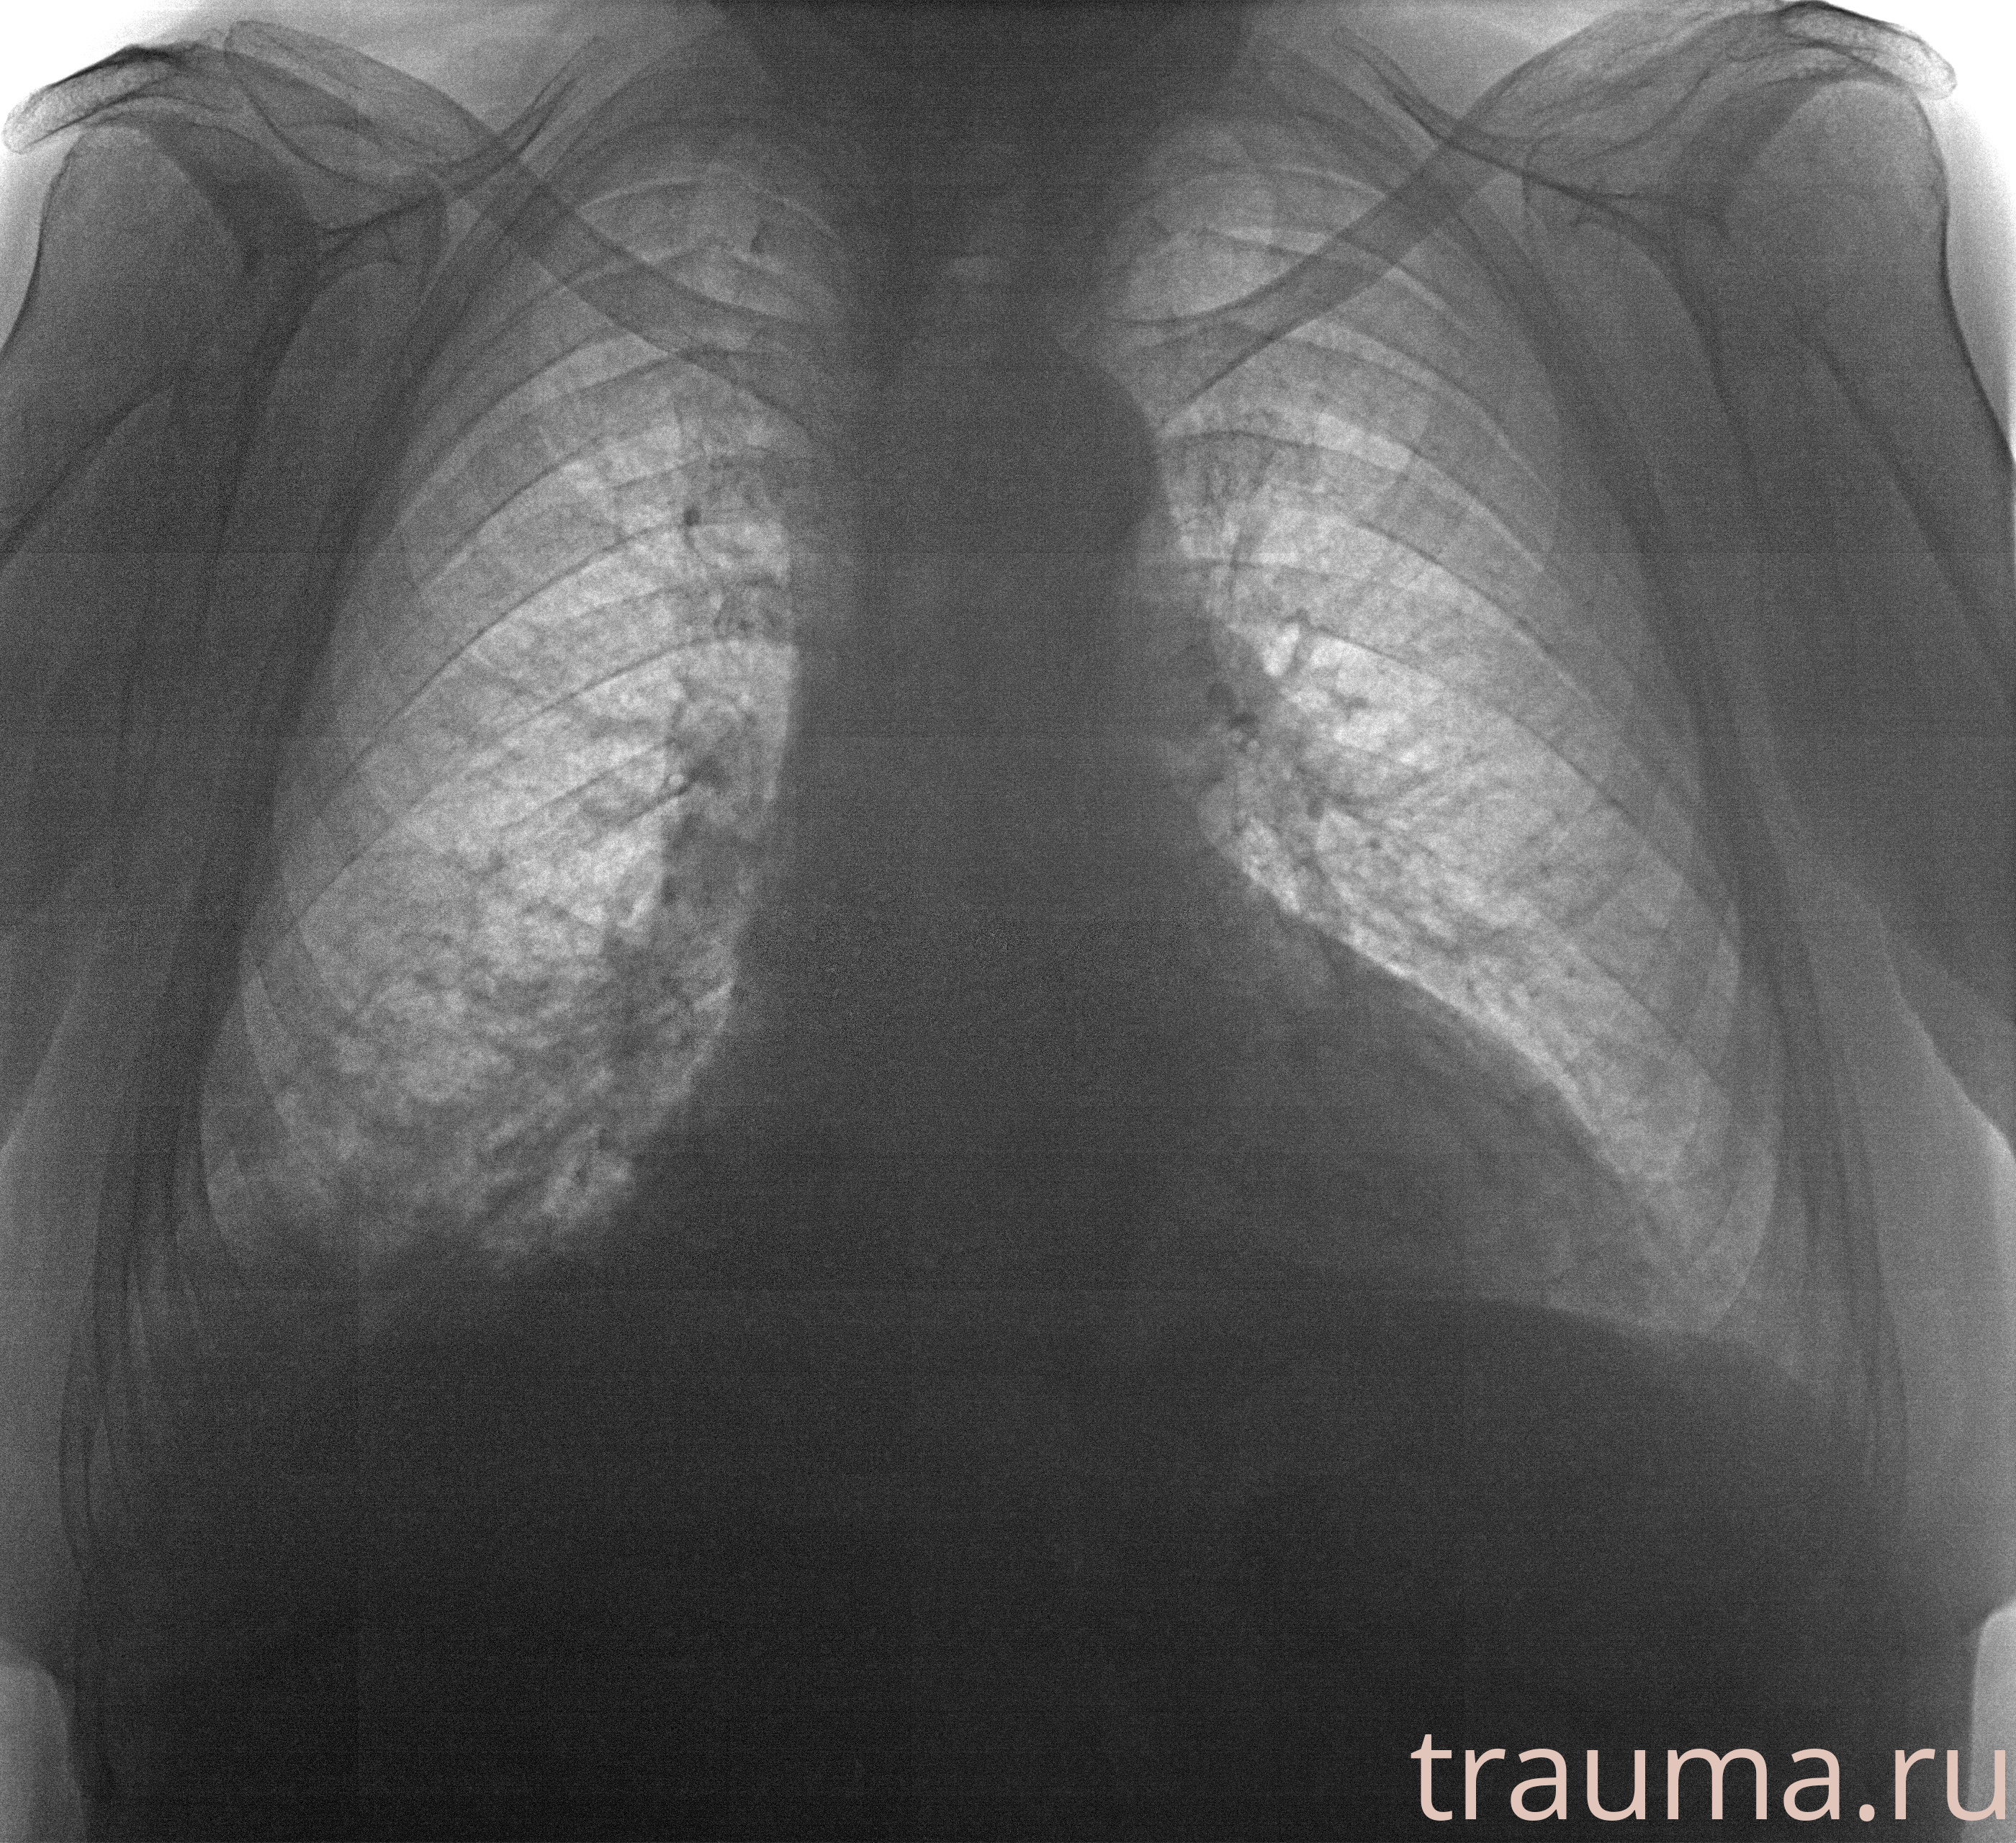

Рентгенограммы

Рентген на дому: по вашему адресу приезжает врач-рентгенолог, травматолог-ортопед с мобильным рентгеновским аппаратом, проводит диагностику травмы или заболевания, делает необходимые рентгенограммы, дает рекомендации по дальнейшему лечению. Получить качественные снимки в домашних условиях возможно благодаря уникальной методике, разработанной МосРентген Центром для института  Склифосовского

при переломе шейки бедра и пневмонии от компании МосРентген Центр - партнера Института имени Склифосовского